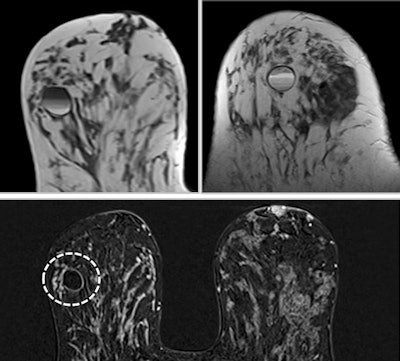

On MRI, the four signs of breast implant rupture are the linguine sign (an elastometric shell of a ruptured implant floating within silicone gel), the keyhole sign (focal silicone invagination between the inner shell and fibrous capsula), the salad oil drop sign (silicone gel mixed with reactive subcapsular fluid), and the subcapsular lines sign (hypointense lines surrounded by silicone gel that run parallel to the fibrous capsule). If only the salad oil drop sign is visualized, it is impossible to conclude that the implant exhibits an intracapsular rupture, they wrote.